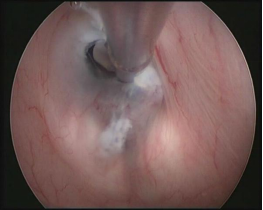

CASE1 病人***,男,67岁,因额部巨大脑膜瘤行开颅手术,术后并发颅内感染,经综合治疗后远期并发脑积水入院。入院时患者亲人不能相识、大小便失禁、行走不能。入院经过全面检查后,在全麻下行脑室镜三脑室底造瘘术,术后3周病人认知功能、大小便控制及步态较术前明显好转。(左图为术中过程,右图蓝色箭头示造瘘口,造瘘成功)。

术中照片:主刀医生及助手行脑室镜下第三脑室底造瘘术